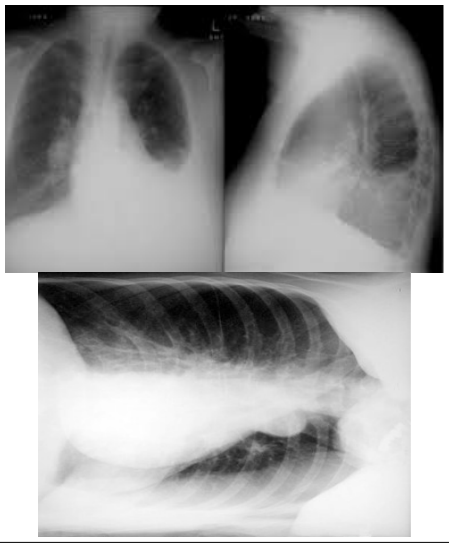

Paciente do sexo masculino, de 69 anos, procura atendimento por perda de peso, 15 kg, em seis meses, hiporexia, sudorese, tosse seca, febre não aferida vespertina, e dispneia aos pequenos esforços progressiva. Procurou atendimento prévio e foi prescrito antibiótico, amoxacilina/clavulanato 875 mg/125 mg, que fez uso por dez dias. Nega melhora dos sintomas. Tabagista, 60 maços/ano. Nega outras patologias ou uso de medicações contínuas. Ao exame, apresenta-se em regular estado geral, eupneico, saturação de oxigênio 95% ar ambiente, frequência cardíaca: 90 bpm. Foram solicitados exames para avaliação, conforme apresentado a seguir: Hemograma: hb 11,0, leucócitos 11.000, bastões 2%, neutrófilos 60%, plaquetas 235.000. PCR 10. Raio X de tórax:

Paciente do sexo masculino, de 69 anos, procura atendimento por perda de peso, 15 kg, em seis meses, hiporexia, sudorese, tosse seca, febre não aferida vespertina, e dispneia aos pequenos esforços progressiva. Procurou atendimento prévio e foi prescrito antibiótico, amoxacilina/clavulanato 875 mg/125 mg, que fez uso por dez dias. Nega melhora dos sintomas. Tabagista, 60 maços/ano. Nega outras patologias ou uso de medicações contínuas. Ao exame, apresenta-se em regular estado geral, eupneico, saturação de oxigênio 95% ar ambiente, frequência cardíaca: 90 bpm. Foram solicitados exames para avaliação, conforme apresentado a seguir: Hemograma: hb 11,0, leucócitos 11.000, bastões 2%, neutrófilos 60%, plaquetas 235.000. PCR 10. Raio X de tórax: